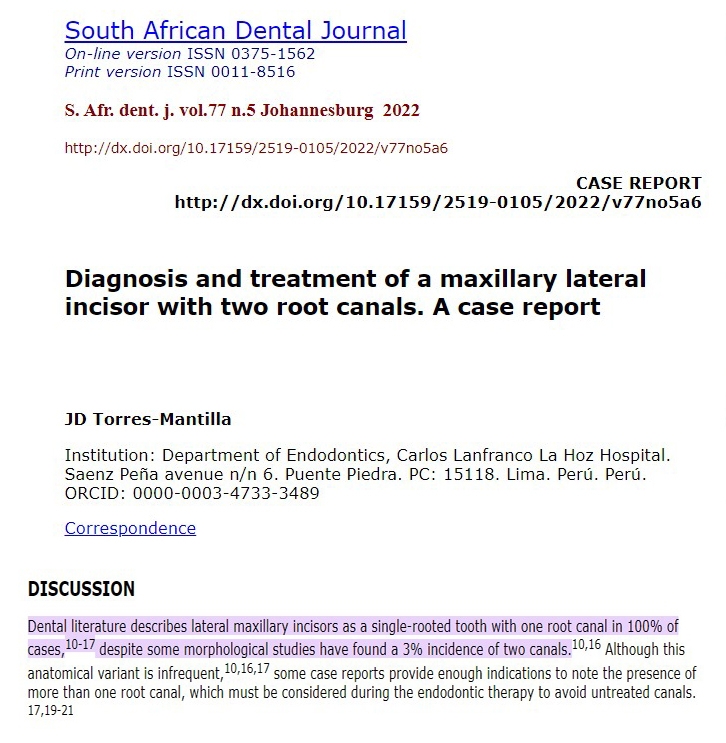

A questo punto, sembra evidente che la radice accessoria debba avere un canale sondabile. Il Dr. Natalini, dopo una ricerca approfondita, trova alcuni (pochi) casi simili. Incisivi laterali superiori vengono definiti “estremamente rari”, con percentuali dallo 0 al 3%.

Le ricerche messe in campo per approfondire casi simili

Le ricerche messe in campo per approfondire casi simili

Nuova sintomatologia a distanza di 16 mesiA questo punto, sembra evidente che la radice accessoria debba avere un canale sondabile. Il Dr. Natalini, dopo una ricerca approfondita, trova alcuni (pochi) casi simili. Incisivi laterali superiori vengono definiti “estremamente rari”, con percentuali dallo 0 al 3%.

Le ricerche messe in campo per approfondire casi simili

Le ricerche messe in campo per approfondire casi similiViene programmato un nuovo appuntamento per rimuovere il composito e rientrare nel sistema endodontico del 2.2, nella speranza questa volta di poter reperire il secondo canale, altrimenti ci si troverebbe nella situazione di essere costretti alla rimozione chirurgica della radice accessoria.